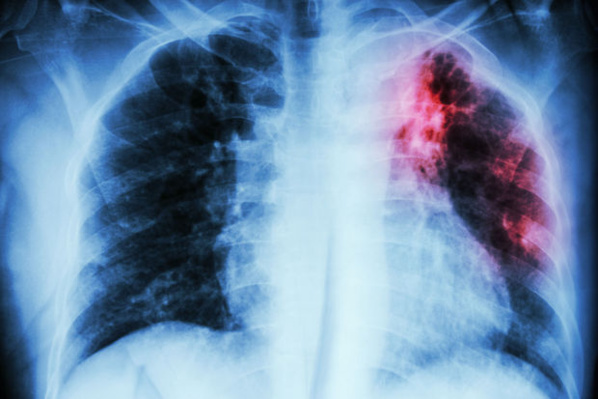

La tuberculose, un problème de santé publique en Mauritanie (Officiel)

La tuberculose constitue un « sérieux problème » de santé publique en Mauritanie, a affirmé samedi à Nouakchott, le Secrétaire général du ministère de la santé, Ahmed Ould Sid’Ahmed Ould Dié.« En Mauritanie, la tuberculose constitue un sérieux problème de santé publique. C’est pourquoi, l’Etat assure la prise en charge complète de tous les malades de la tuberculose, avec une attention particulière accordée aux franges les plus défavorisées », a dit M. Dié lors de la célébration de la Journée mondiale de lutte contre la tuberculose.